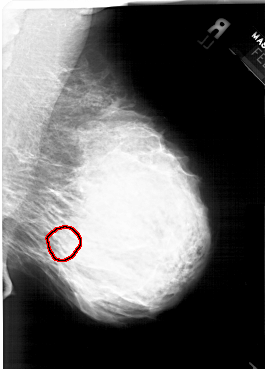

A_1564_1.RIGHT_MLO

RIGHT_MLO LINES 6271 PIXELS_PER_LINE 4501 BITS_PER_PIXEL 12 RESOLUTION 43.5 OVERLAY

FILE: A_1564_1.RIGHT_MLO.OVERLAY

TOTAL_ABNORMALITIES 1

ABNORMALITY 1

LESION_TYPE CALCIFICATION TYPE PLEOMORPHIC DISTRIBUTION SEGMENTAL

ASSESSMENT 4

SUBTLETY 4

PATHOLOGY BENIGN

TOTAL_OUTLINES 1

BOUNDARY